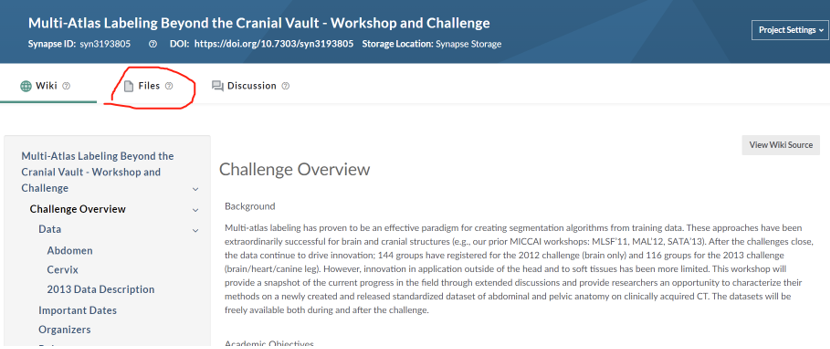

首先,打开全能竞赛官网,

https://www.synapse.org/#!Synapse:syn3193805/wiki/217752,可以看到如下画面,点击红框选中区域,进入数据区。